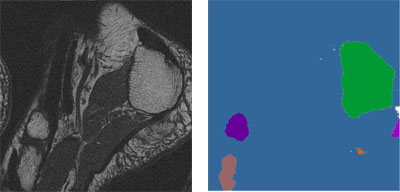

Innymi prowadzonymi badaniami była analiza zdjęć MRI przedstawiających poprzeczny przekrój przez ludzką stopę. Celem tych badań było określenie wpływu rozdzielczości tomografu oraz stosowanych sekwencji (Spin echo, Flash 3D) na teksturę kości śródstopia i pięty (rys. 8). Inne prace dotyczą segmentacji takich obrazów z wykorzystaniem sieci synchronicznych oscylatorów. Celem segmentacji jest wydzielenie obrazu kości pięty i śródstopia od pozostałych tkanek. Wynik segmentacji przykładowego obrazu pokazano na rys. 9. Potencjalnym zastosowaniem takich badań może być wspomaganie diagnostyki osteoporozy.

| Rys. 9 Obraz MRI poprzecznego przekroju przez stopę (a) oraz wynik jego segmentacji (b) |